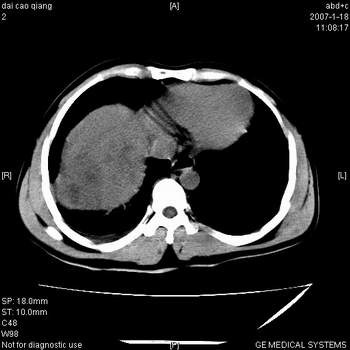

肝右叶巨块型肝癌,伴癌栓形成.

符合肝癌强化特点,患者有无乙肝病史?

符合巨块型肝癌表现:

1、平扫低密度,增强后表现为快进快出。

2、动脉期可见迂曲的动脉供血血管

3、并可见门静脉右支癌栓形成

4、可见假包膜

5、腹主动脉旁结节影,考虑肿大淋巴结。

肝右叶巨大不均匀低密度肿块,前缘有假包膜,增强明显的呈快进快出表现,门脉右支有癌栓,病人虽然年轻但还是首先考虑肝右叶巨块形肝癌,病人血象高只能说有合并感染。不支持肝脓肿。